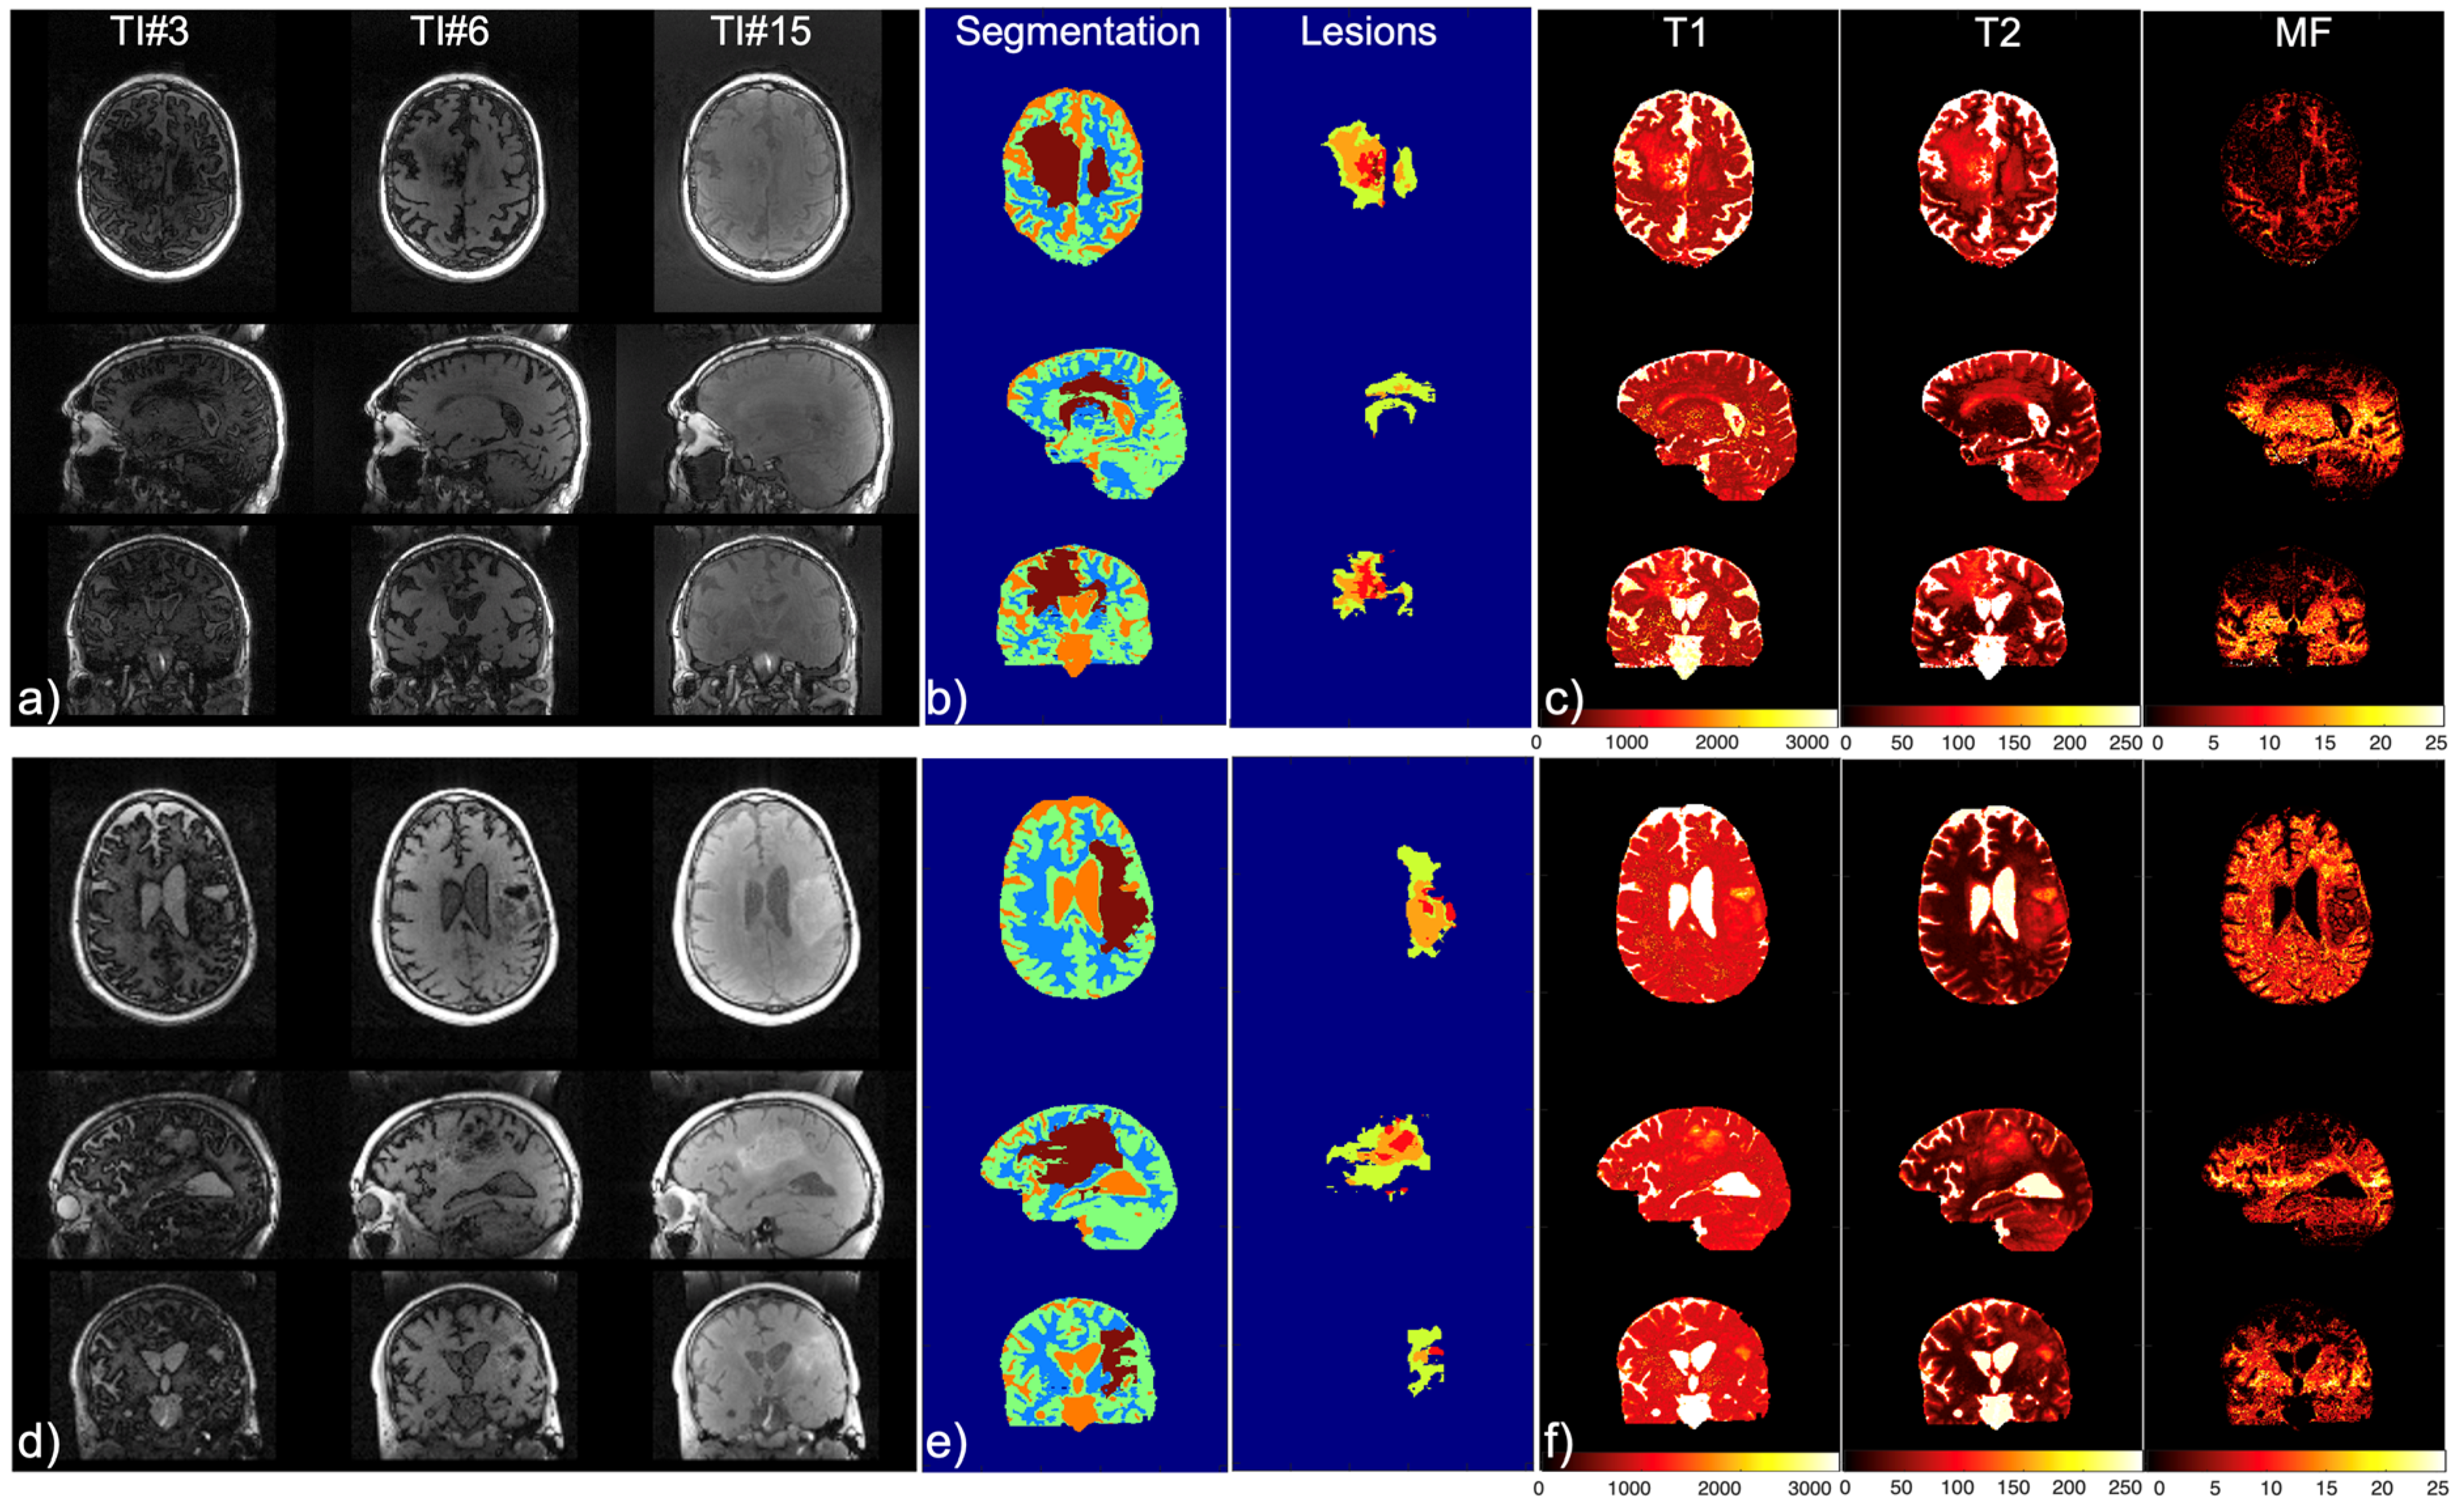

2.6. Patient Scans

3. Results